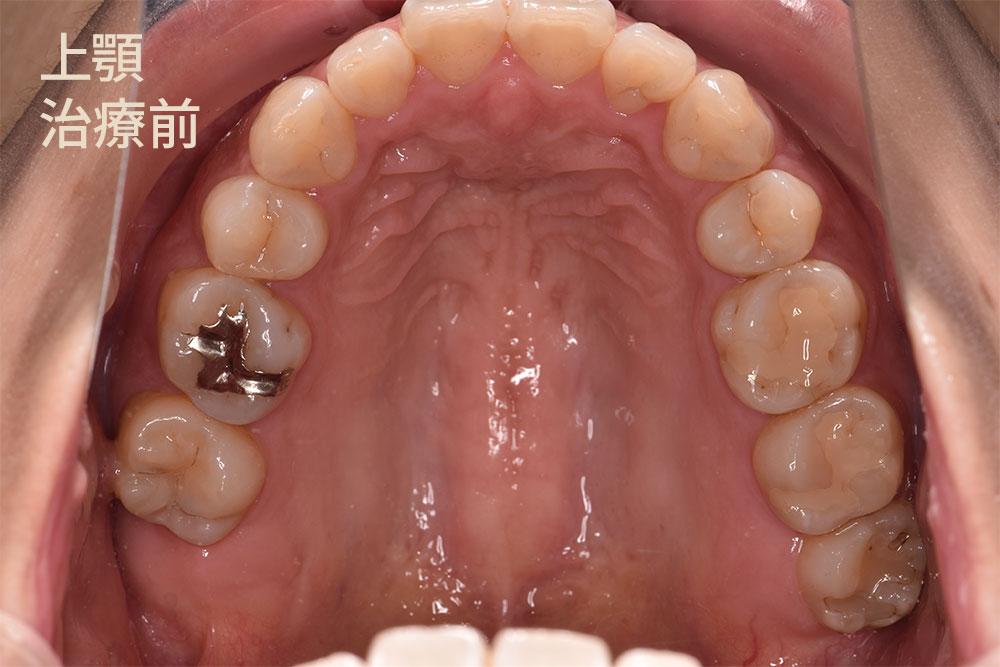

30代女性で銀歯を白い歯にしたいとのことでご来院されました。銀歯で治療されている歯は5箇所ありました。ご本人はいつ治療をしたか覚えていらっしゃらないくらい治療をしてから期間が経過していました。今回は銀歯の範囲に応じて、小さな箇所にダイレクトボンド治療、銀歯の大きな箇所(隣の歯と接している)へはセラミックインレー治療を適用できる判断し、治療を開始しました。

右上第一大臼歯(緑矢印)の咬む面に銀歯があるのがわかります。一見すると異常はないように見えます。

セラミックインレー治療のメインはセラミックスです。ダイレクトボンド治療との違いは、適用症例が異なります。セラミックインレー治療はダイレクトボンド治療と比べて、治療をする歯の範囲が大きくなります。今回の症例のように隣の歯に及ぶ銀歯での治療をされている場合、強度の面でセラミックインレー治療を適用します。( 黄色い矢印 )